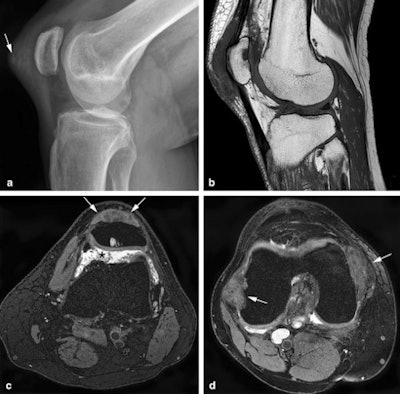

MRI is the modality of choice to diagnose TGCTs and discriminate between subtypes, and it can also provide a preoperative map before synovectomy, the mainstay of treatment, the authors noted.

"Since the arrival of colony-stimulating factor 1-receptor inhibitors, a novel systemic therapy for D-TGCT patients with relapsed or inoperable disease, MRI is key in assessing treatment response," they noted. "As recurrence after treatment of D-TGCT occurs more often than in lateral TGCT, follow-up imaging plays an important role in D-TGCT."

Reading follow-up MRIs of these diffuse synovial tumors may be a daunting task, they continued, and it's important to provide a systematic approach to assess the knee synovial recesses, highlight D-TGCT imaging findings, and combine these into a structured report. In addition, it is important to bear in mind differential diagnoses mimicking D-TGCT, potential pitfalls, and evaluation of tumor response following systemic therapies.